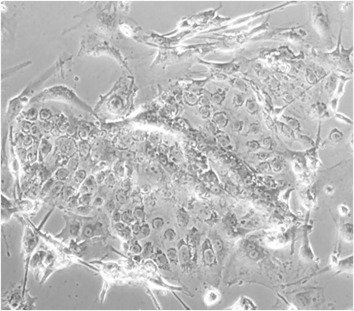

We are among those pioneers to apply and develop single-cell RNA sequencing (Smart-seq, Smart-seq2, LCM-seq etc). More tools to answer all these interesting questions are mouse disease models, human iPSC culture and differentiation, organoid culture, human sample cohorts and registry data together with other key cellular and molecular assays.